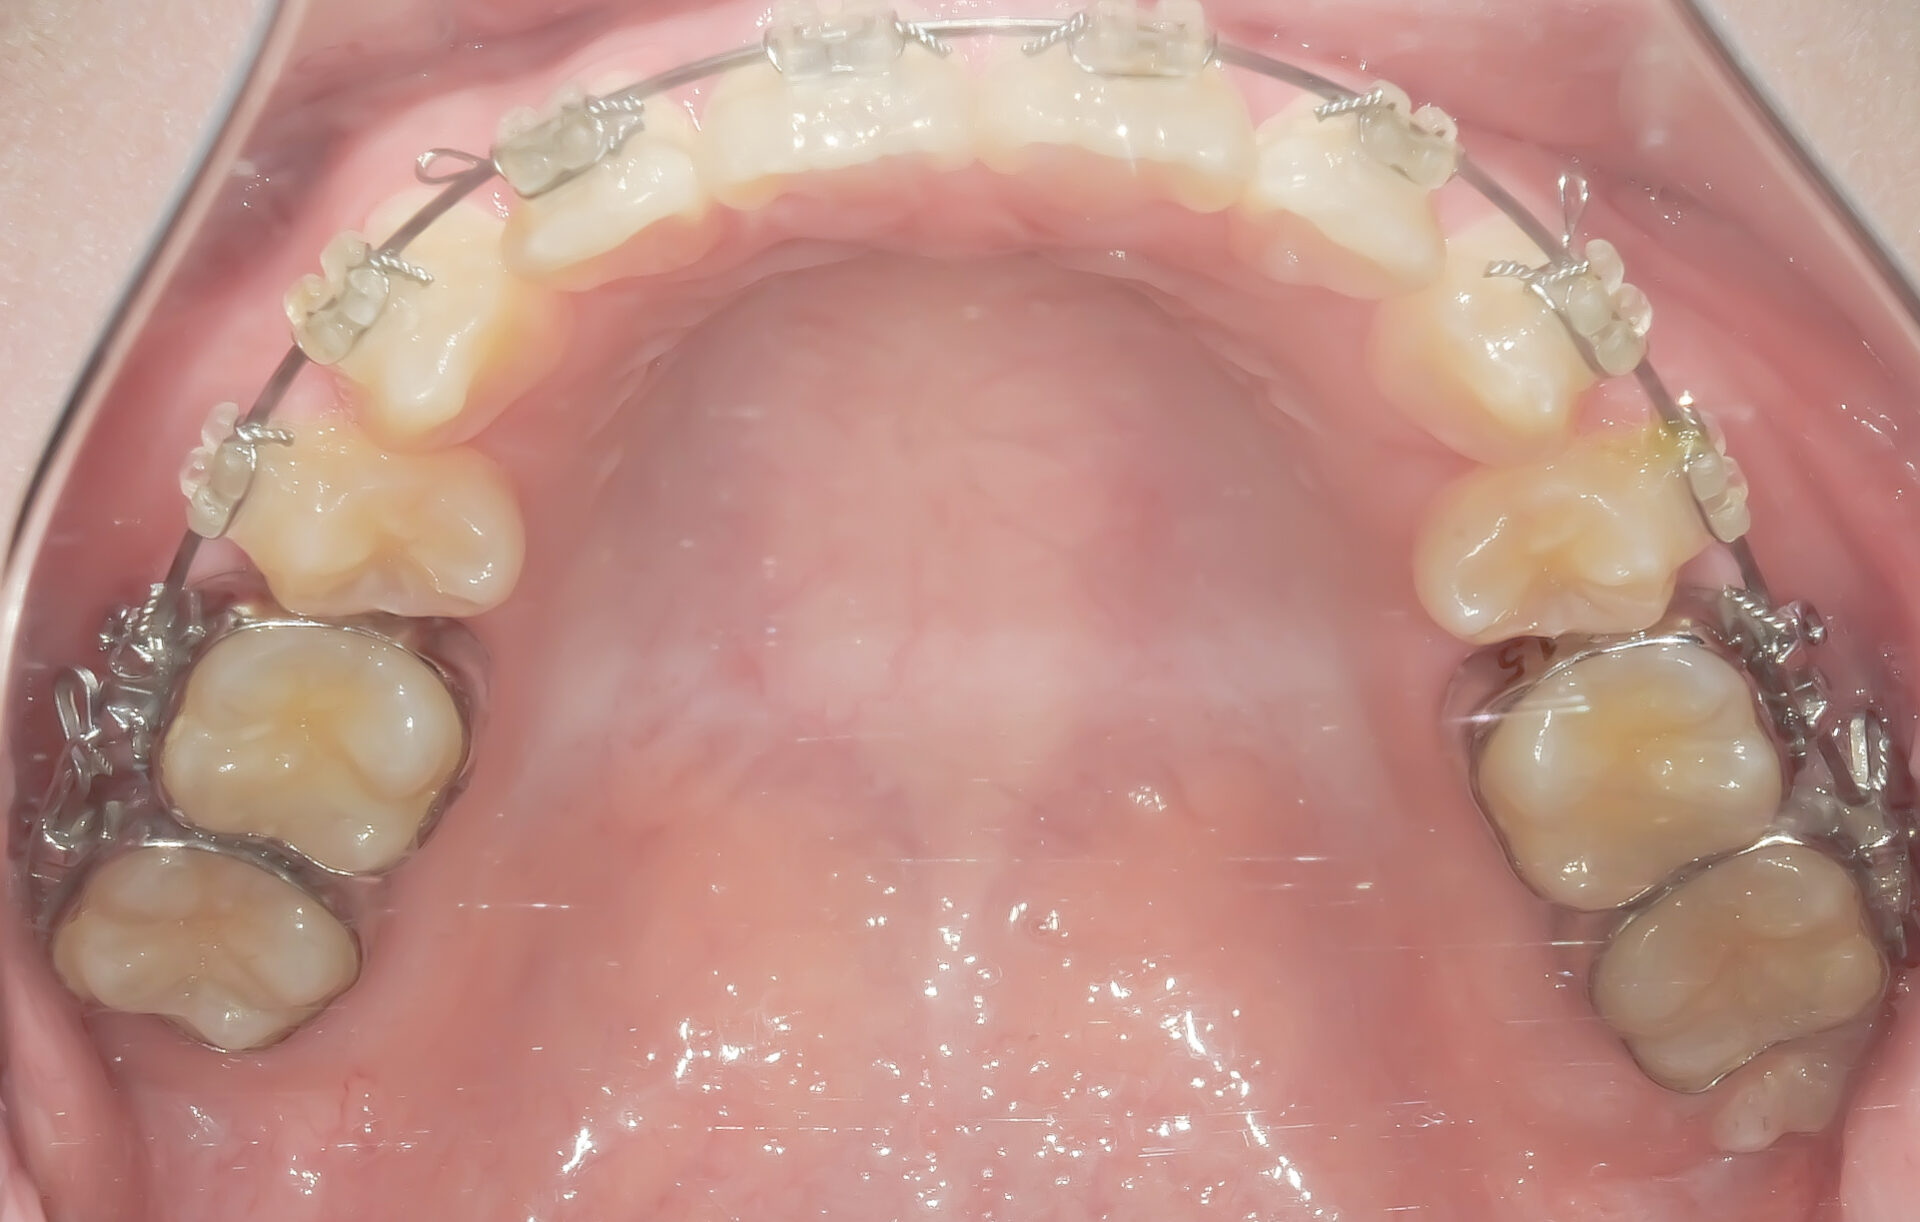

After

上顎にワイヤーが装着されています。

上顎の前から4番目の歯(第一小臼歯)は抜去されており、そのスペースを使って叢生を改善していきます。

治療後です。叢生がなくなりきれいに並んでいます。